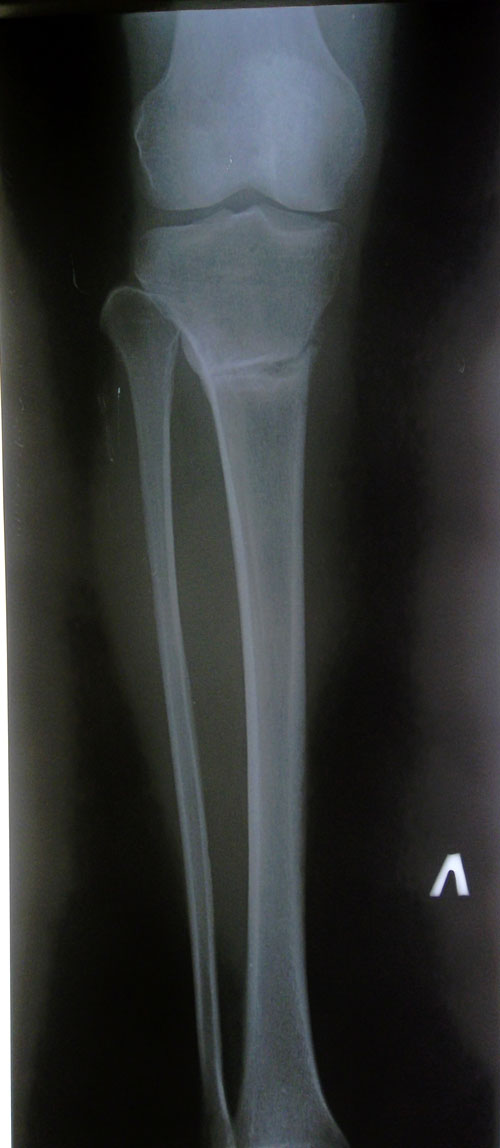

Рентгеновские снимки в 2 месяца после операции.

По рентгеновским снимкам сращение идёт хорошо, но ещё немного походим. В 3 месяца можно приезжать на снятие аппаратов. Дату приезда согласуйте со мной!

Рентген контроль в 1,5 месяца после снятия аппаратов.

Отличное сращение! Рекомендации: каблуки (пока) 5-6 см, не более. Через 1,5 месяца рентген + фото ножек. Курс массажа и физио прошли? Качайте внутренний контур!